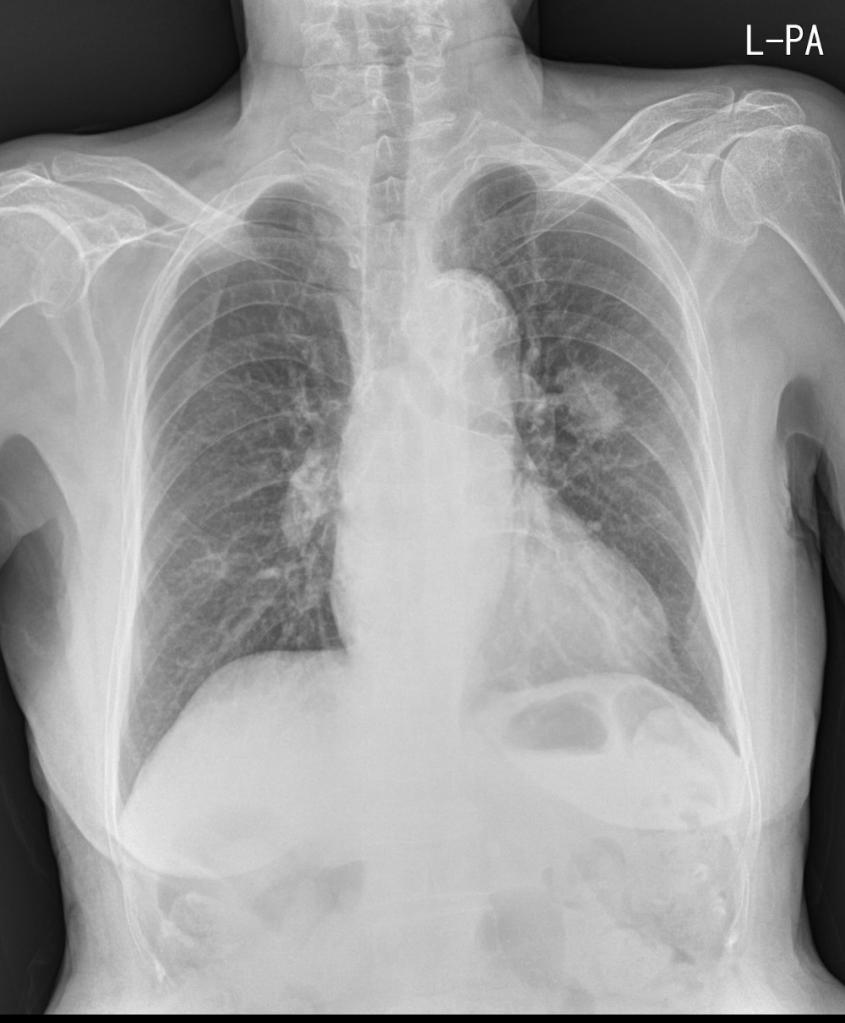

91세 여자 환자로, CT에서 왼쪽 폐에 폐암이 발견되었으나, 고령과 전신상태가 여의치 않아 수술을 포기한 분의 단순 흉부X선 영상입니다.

이전에 여러차례 촬영했던 Chest PA view는 물론 CT에서도 분명히 확인했던 왼쪽 폐의 암덩어리가 AP view에서는 확인되지 않습니다. 이렇게만 보면, 기적적으로 며칠만에 암덩어리가 사라졌든지, 과거 폐암으로 진단되었던 병변이 폐암이 아니라 국소적인 폐렴이었다 며칠만에 호전되었을 가능성도 제기할 수 있을겁니다.

폐에 병변이 의심되는 경우 가장 기초적인 영상검사는 단순흉부X선검사입니다. 특별한 제약사항이 없다면 기본적으로 서있는 자세로 Chest PA view영상을 촬영하는 것이 원칙인데, 왜 AP view가 아닌 PA view를 촬영해야 하는지를 극명하게 보여주는 사례 같아서 올려봅니다.

또한, 의대생이나 영상의학을 전공하지 않은 분이라면 위의 영상들만 보고 Chest PA view인지 AP view인지 정확하게 구별하지 못하는 분들이 있을 수 있지만, 자세히 들여다보면 AP view와 PA view를 구분할 수 있는 중요한 특징들이 잘 드러나있는 영상들입니다. 영상의학과에서 기사분들이 촬영하면서 라벨을 잘못 붙혀서 AP view영상임에도 불구하고 PA view로 잘못 기재되는 경우들이 종종 있고, 이게 나중에 문제가 되는 경우도 있기 때문에 이 둘을 구분하는 건 시험공부로든, 실제 임상영역에서든 상당히 중요한 부분이라 생각합니다.

위의 영상들을 가지고 AP view와 PA view의 구분을 할 수 있는지 잠깐 점검해보는 것도 괜찮을거라 봅니다.